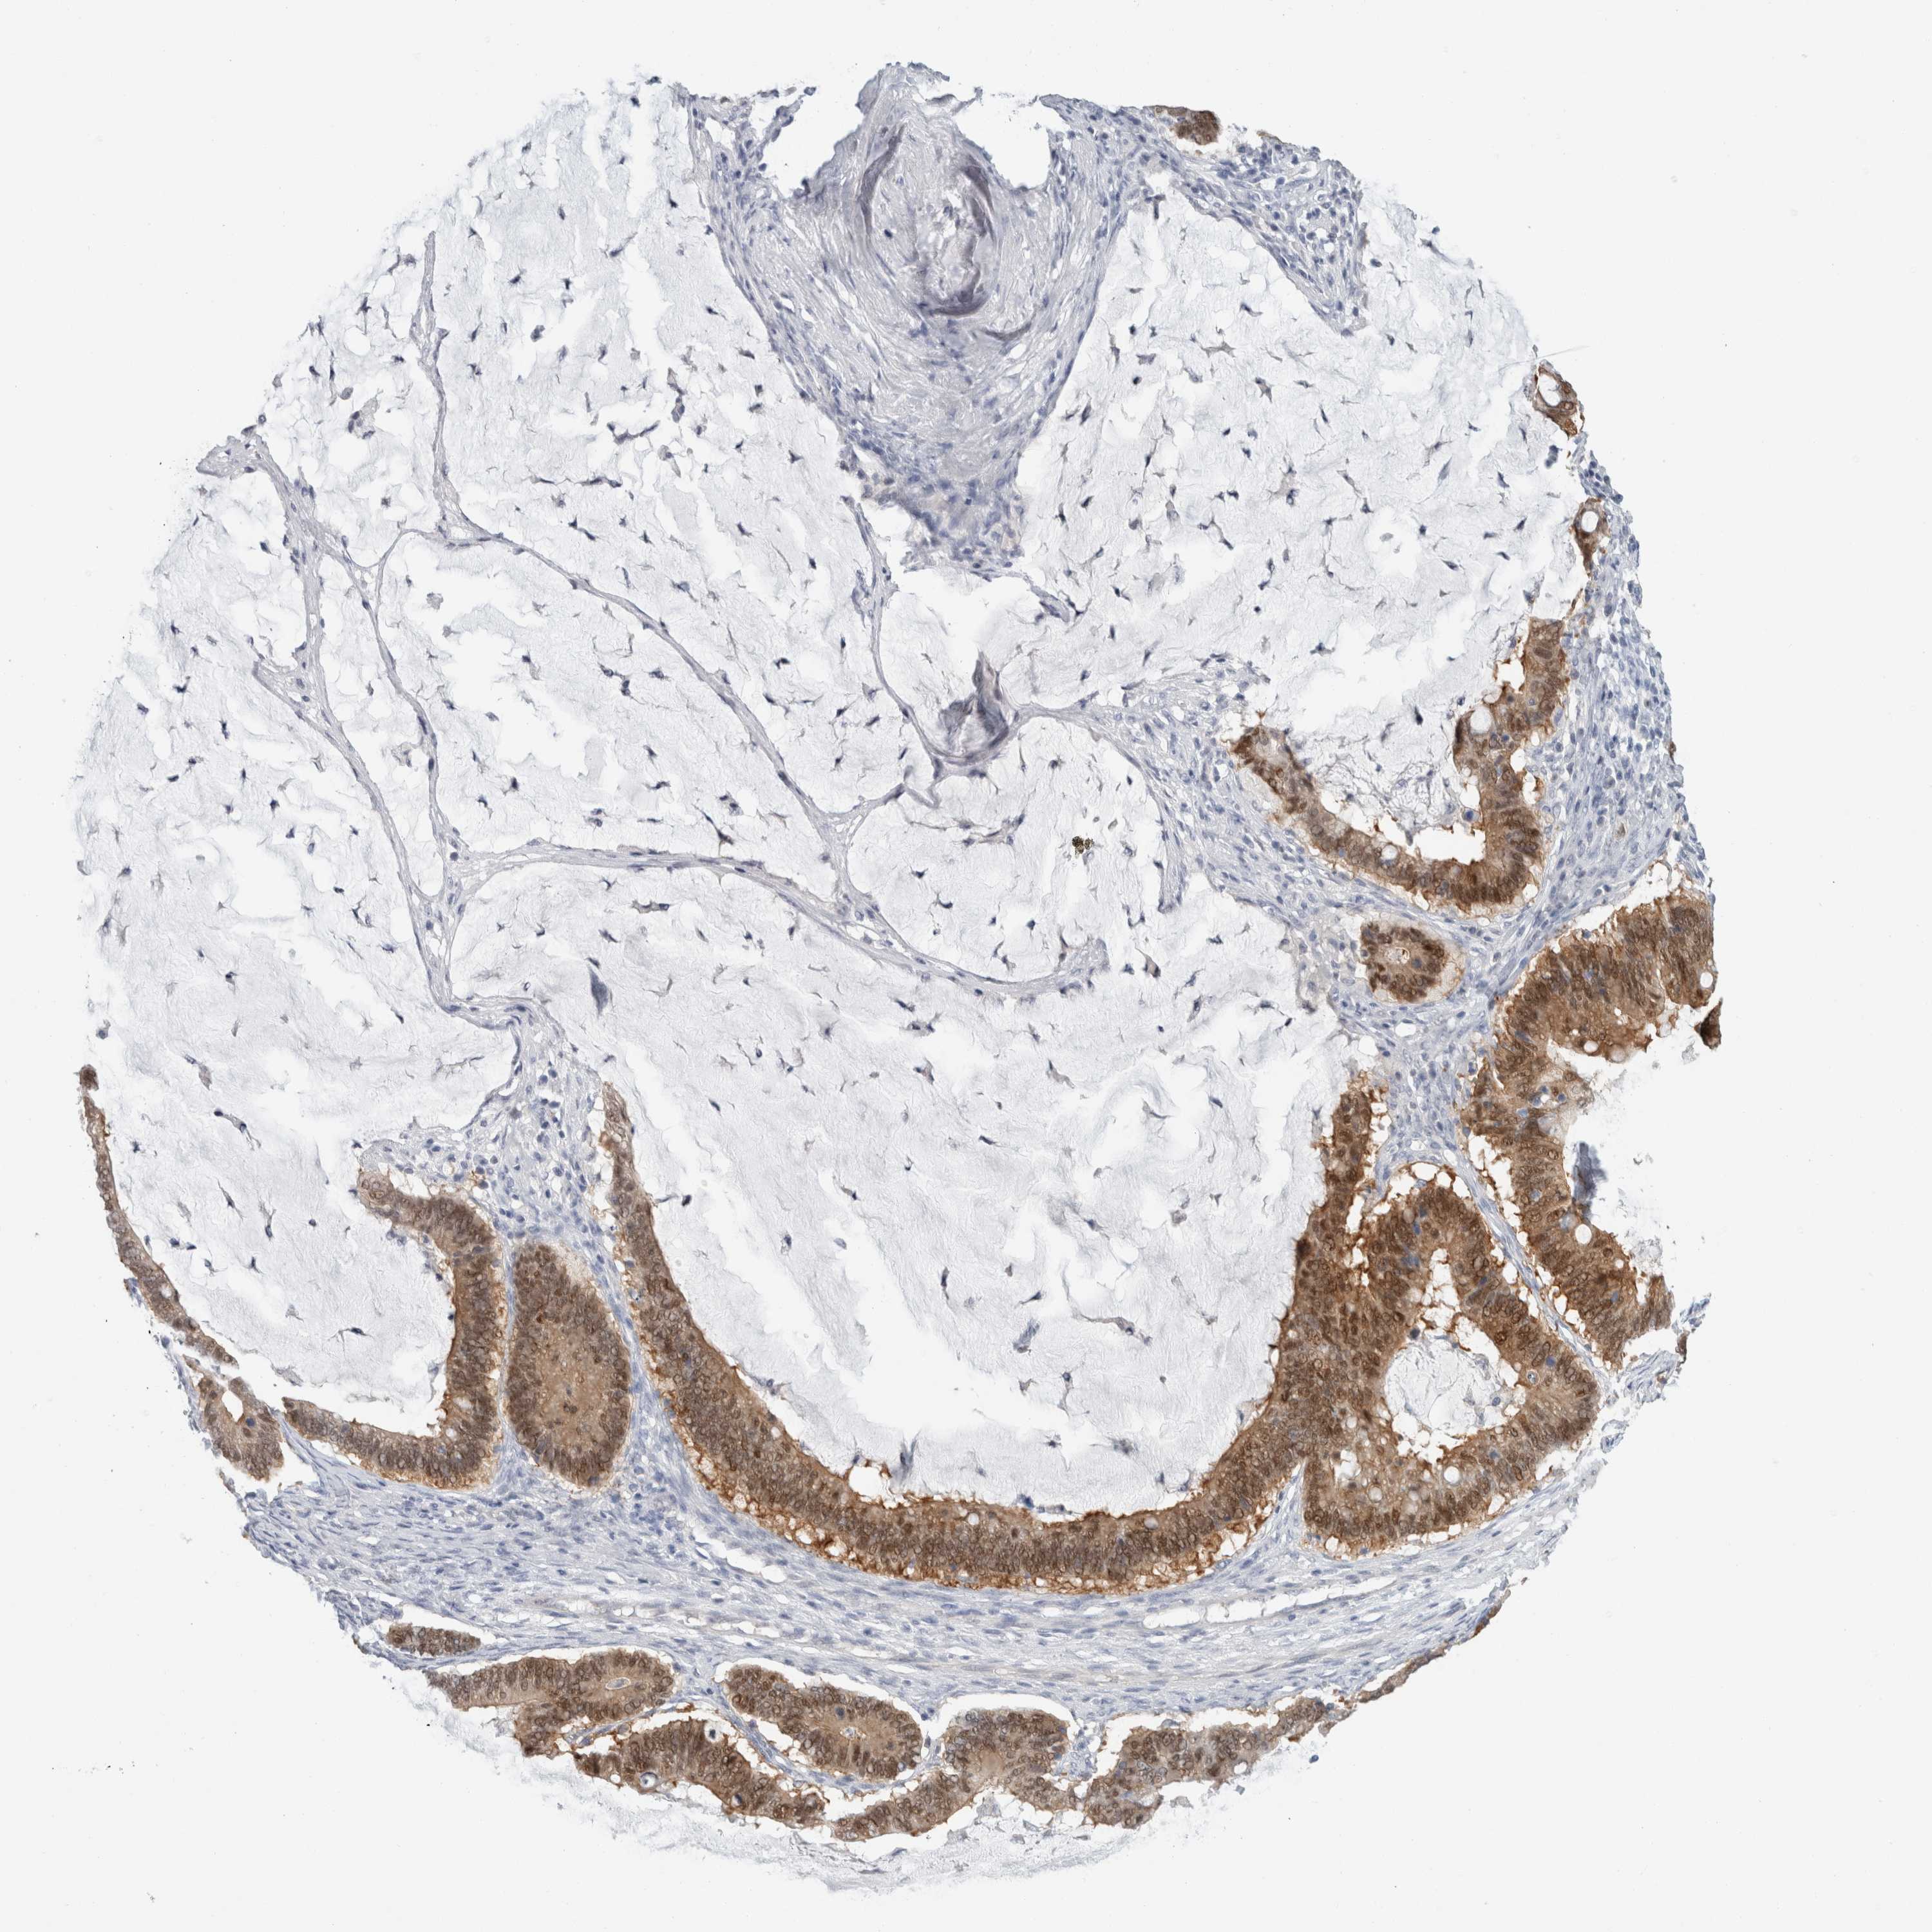

OVARIAN CANCER - Protein expressioni

A mouse-over function shows sample information and annotation data. Click on an image to view it in a full screen mode. Samples can be filtered based on level of antibody staining by selecting one or several of the following categories: high, medium, low and not detected. The assay and annotation is described here.

Note that samples used for immunohistochemistry by the Human Protein Atlas do not correspond to samples in the TCGA dataset.

Antibody stainingi

Antibody staining in the annotated cell types in the current human tissue is reported as not detected, low, medium, or high, based on conventional immunohistochemistry profiling in selected tissues. This score is based on the combination of the staining intensity and fraction of stained cells.

Each image is clickable and will lead to virtual microscopy that enables deeper exploration of all samples and also displays staining intensity scores, fraction scores and subcellular localization as well as patient and tissue information for each sample.

Antibody HPA011337

Cystadenocarcinoma, serous, NOS